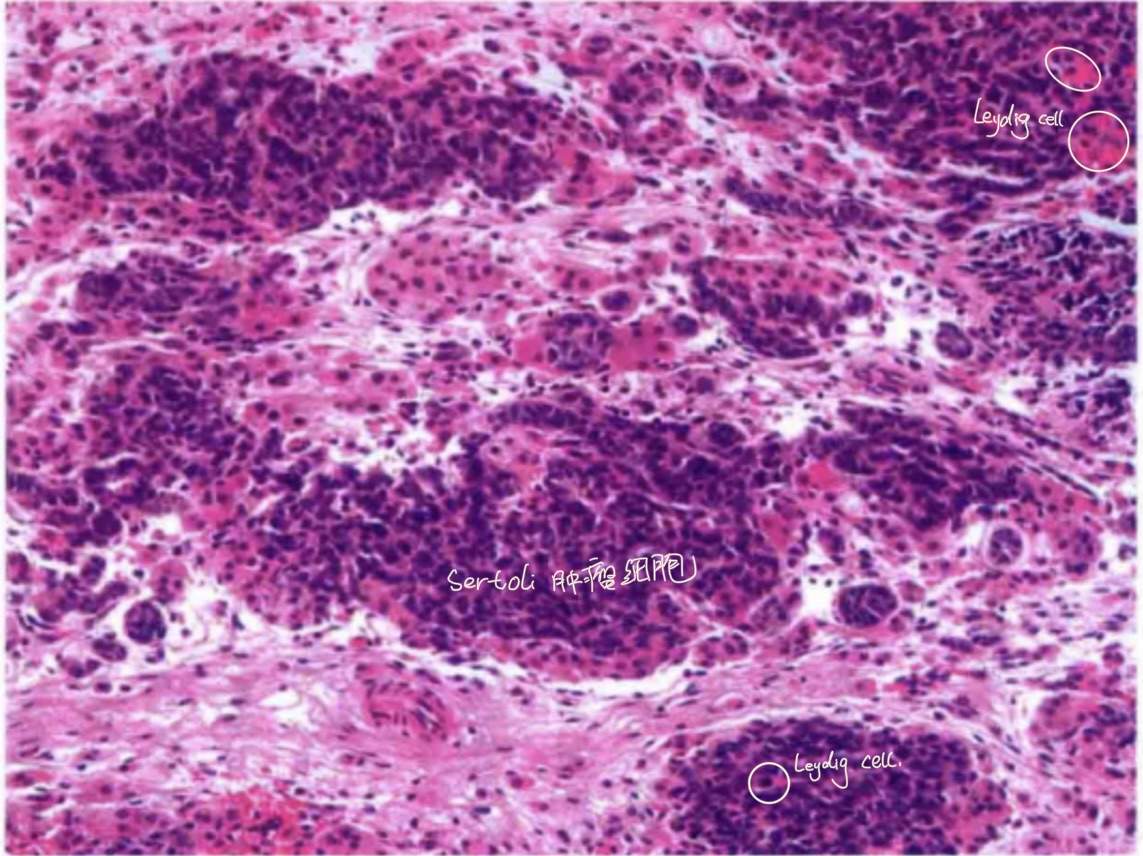

在睾丸中叫Sertoli细胞(支持细胞)如图:

正如上图所描绘的那样,睾丸的间质细胞的另外一个大名鼎鼎的名字就是—Leydig细胞。

最后,它有个特殊类型:网状型Sertoli-Leydig细胞肿瘤,如图:

不规则分枝状,细长,狭窄,常呈裂隙样。